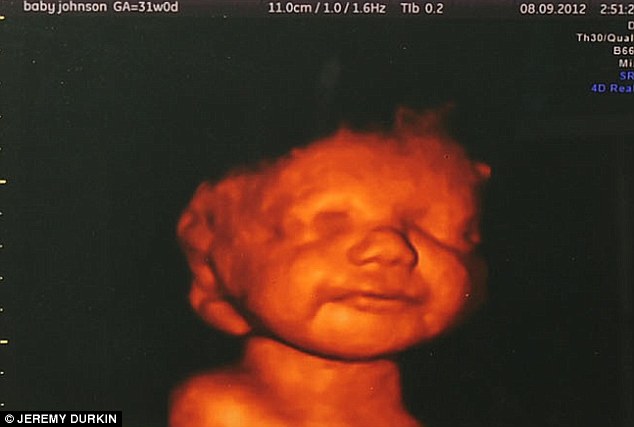

Angyali mosolya menthette volna meg a babát

Orvosai figyelmeztetése ellenére Katyia Rowe egyszerűen képtelen volt rászánni magát az abortuszra, miután egy háromdimenziós ultrahangfelvételen először megpillantotta születendő kisbabája mosolyát. Katyia tisztában volt vele, hogy súlyosan sérült kisfia egész életében 24 órás felügyeletre szorulna, mivel soha nem lenne képes megtanulni járni vagy beszélni, ennek ellenére képtelen volt elvetetni a méhében növekvő magzatot, miután az ultrahangos felvételen tisztán látta, amint mosolyog és integet a kisbaba. Katyia úgy döntött, hogy megszüli sérült gyermekét, de tragikus módon Lucian mindössze kilenc óráig volt képes életben maradni. A szomorú végkifejlet ellenére az édesanya egy pillanatra sem bánta meg, hogy életet adott kisfiának, ugyanis az a néhány perc, amíg a karjaiban tarthatta Luciant, mindenért kárpótolta őt.